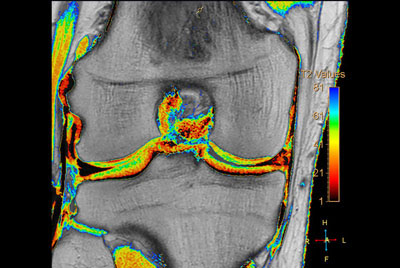

SmartSpeed Traumatic Knee imaging

SmartSpeed 2 min Knee imaging

Knee ACL repair

High quality Knee imaging in short scan times

Knee imaging with Compressed SENSE

Knee exam with/without Compressed SENSE

Knee Imaging with Cartilage Assessment

3D Knee imaging with MSK VIEW

Comprehensive 3D knee imaging with MSK VIEW